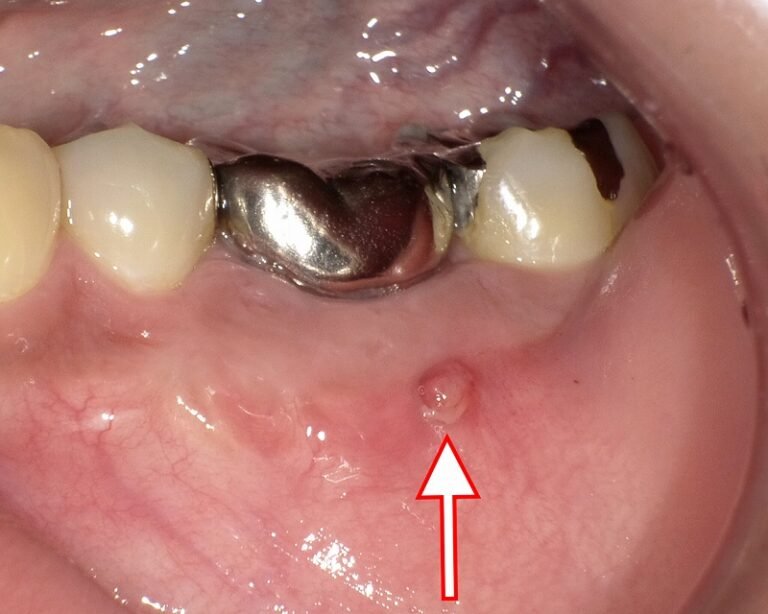

医疗法人微笑协会深泽牙科诊所筱崎

什么是瘘管?解释脓液痛苦而危险的排出途径